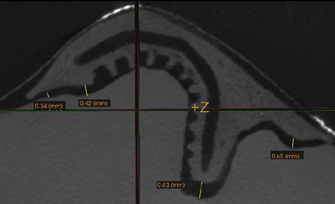

Fig 3. A 3D printed scaffold was designed using CAD software to fit a peri-osseous defect in a human patient. The scaffold consisted of a region with channels designed to support oriented PDL tissue formation and a region for the regeneration of osseous tissue. Fig 3: baseline;

Fig 4: defect model; Fig 5 through Fig 7: internal, tilted, and side views of scaffold, respectively; Fig 8 through Fig 10: coronal, middle, and apical

angles, respectively; Fig 11: cross-section diagram; Fig 12: labial scan image. (Images reprinted with permission from Rasperini G, Pilipchuk SP, Flanagan CL, et al. J Dent Res. 2015;94[9 suppl]:153S-157S.)

Figure 3

Fig 4. A 3D printed scaffold was designed using CAD software to fit a peri-osseous defect in a human patient. The scaffold consisted of a region with channels designed to support oriented PDL tissue formation and a region for the regeneration of osseous tissue. Fig 3: baseline;